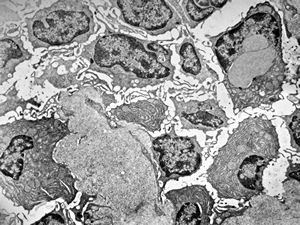

normal seromucinous salivary gland